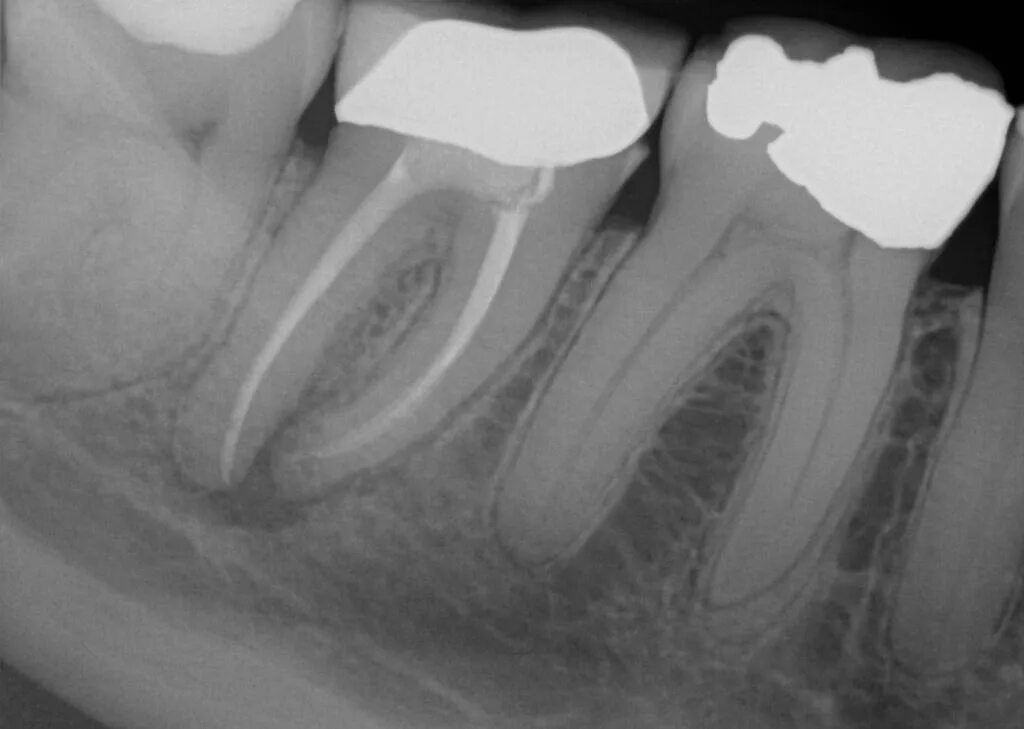

Воспаление зуба после удаления нерва